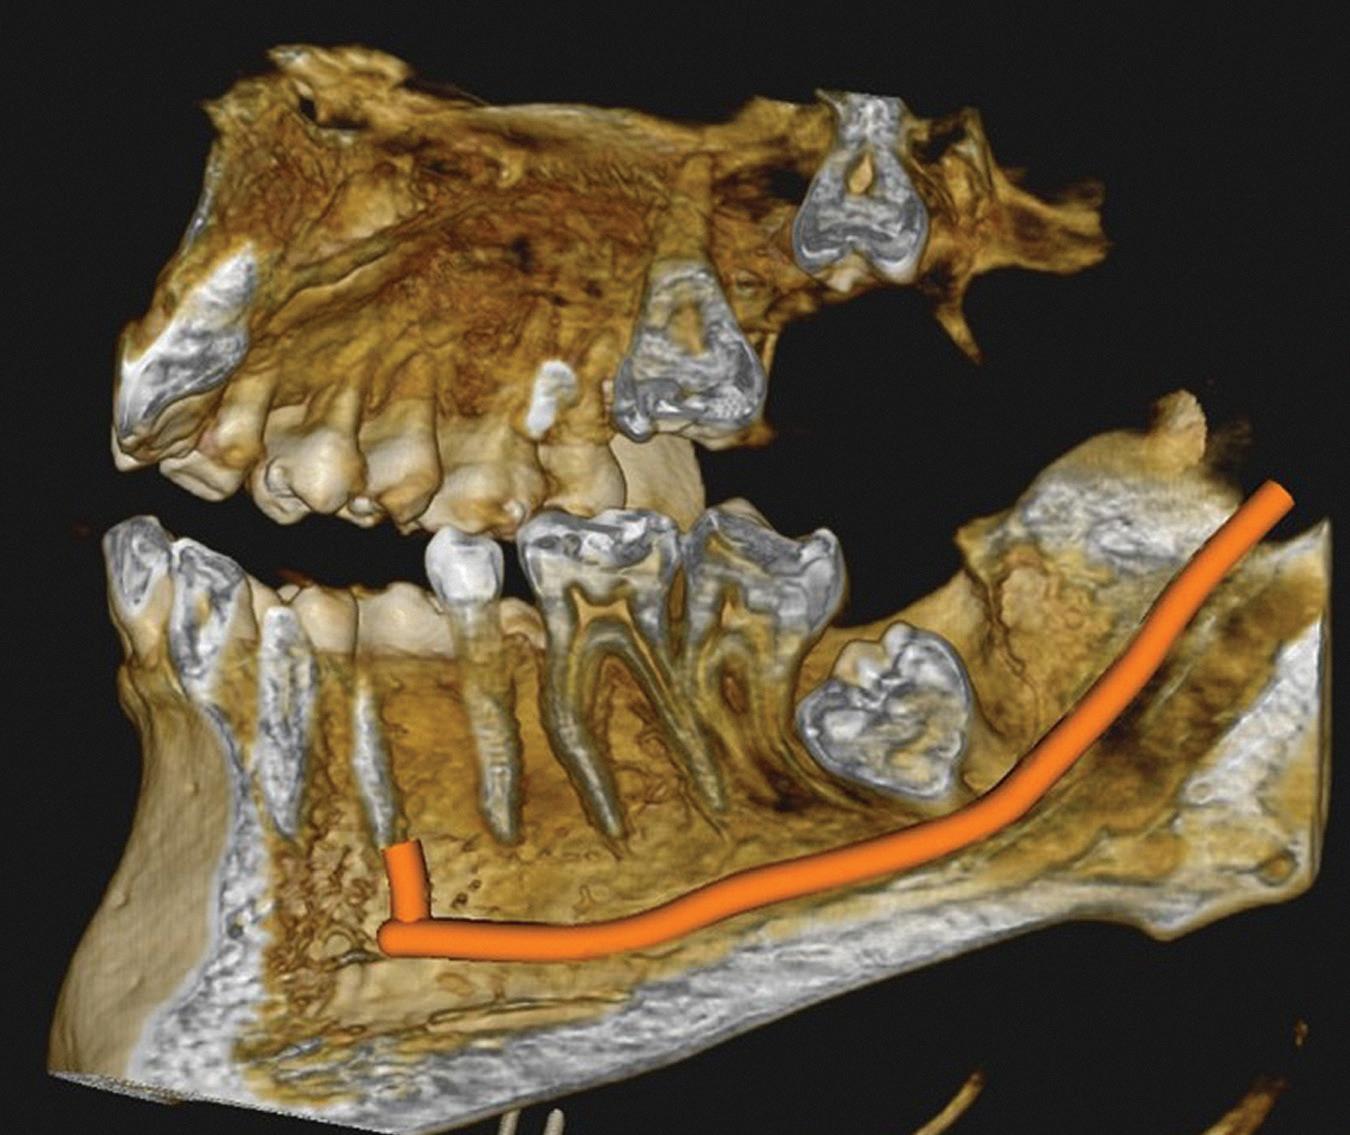

Use technology that saves you clinical time. Lasers? Scanners? Milling machines?. Use technology that increases clinical accuracy and efficiency. Micro scope? CBCT? Use technology that improves diagnostics. Bite analysers. Electronic shade guides.